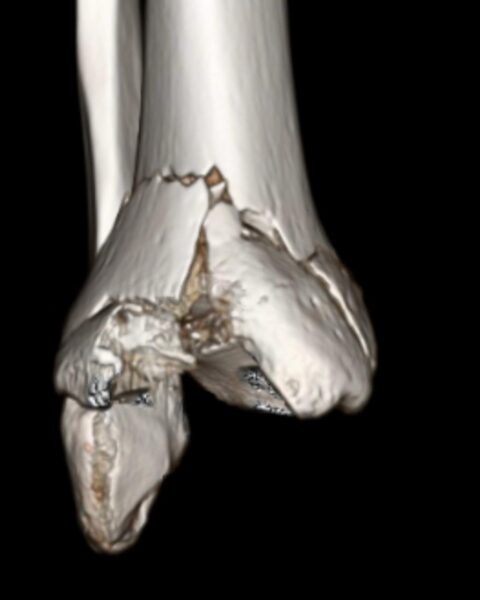

Shattered

Modern Art ~ Feb 2024